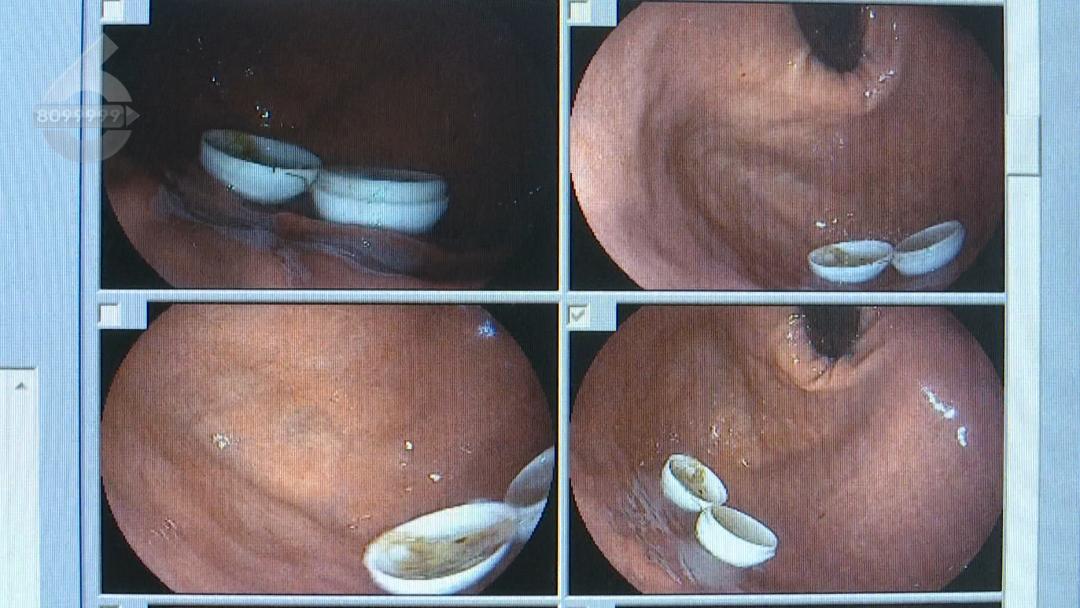

了解患者情况后,医生立即安排胃镜检查,经过检查发现,患者误食的塑料球壳直径约2厘米,经过肠胃蠕动已经分离成了两瓣。

昆明同仁医院消化内镜室主任田建军说:“检查的时候医生就发现,胃部仍然存有白色的牛黄解毒丸的外包装。因为球壳直径比较大,没有办法通过幽门进入我们的小肠,顺次进入到结肠排出体外,一周的时间仍然存在患者体内。还是有取出来的必要性,因为直径比较大,如果是排到更狭窄的肠段,它会引起急性的肠梗阻甚至需要手术来解除梗阻的情况。”

昆明同仁医院消化内镜室主任田建军说:“经过与家属和患者沟通,我们就用专用的医用钳尝试从胃里把直径2厘米的外包装分次取出来。”

在取出塑料球壳的过程中,医生在内镜头端戴上了透明帽,防止取出异物的过程中造成腹部损伤,经过10多分钟的小心操作,滞留在患者胃里的两瓣塑料球壳被成功取出。